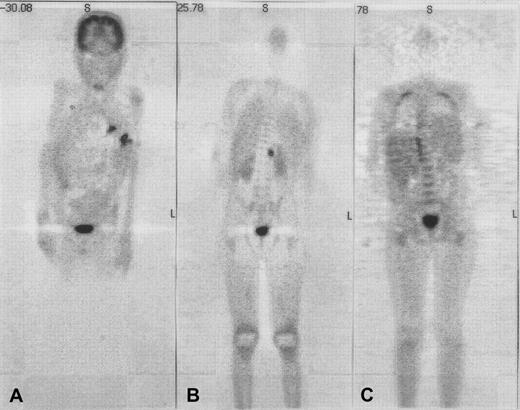

As a result of the development of oxidase activity, therapy-refractory pre-existing infections (3 episodes of life-threatening aspergillosis, 1 episode of severe gastritis due toUstilago) were eradicated in 4 of 4 evaluable patients. In patient 6, healing of a fistula over the rib and normalization of C-reactive protein was observed within the first month after HSCT; resolution of active (hypermetabolic) lesions was complete after 3 months as evidenced by repeat whole-body positron emission tomography (PET) with the use of F18-fluorodeoxyglucose (FDG) (Figure1). An exacerbation of the pre-existingAspergillus pneumonia during aplasia was seen in 3 of 9 patients (nos. 1, 4, and 7), and a diffuse inflammatory pulmonary reaction at the time of neutrophil engraftment in 2 of 6 evaluable patients (nos. 2 and 3). In 4 of the 5 patients, the pneumonia was bilateral, progressed to white lungs, required ventilation, and was not survived. Lung biopsies were considered too invasive to be performed.

Use of coronal emission fluorodeoxyglucose–positron emission tomography (FDG-PET) in patient 6 with multifocal aspergillosis.

Coronal emission FDG-PET before (panels A and B) and 3 months after (panel C) HSCT in patient 6 with multifocal aspergillosis. PET shows multiple lesions in the lungs and a focus in the upper-left psoas with intense FDG uptake before HSCT; these have disappeared at 3 months after HSCT. Physiologic high-FDG uptake is seen in the brain and bladder.